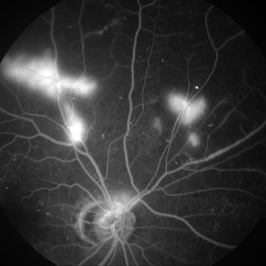

Proliferative Diabetic Retinopathy - Neovascularization Elsewhere

Nov 11 2013 by Gerardo Garcia-Aguirre, MD

Fluorescein angiogram showing leakage secondary to neovascularization in the superior arcades.

Condition/keywords: neovascularization (NV)